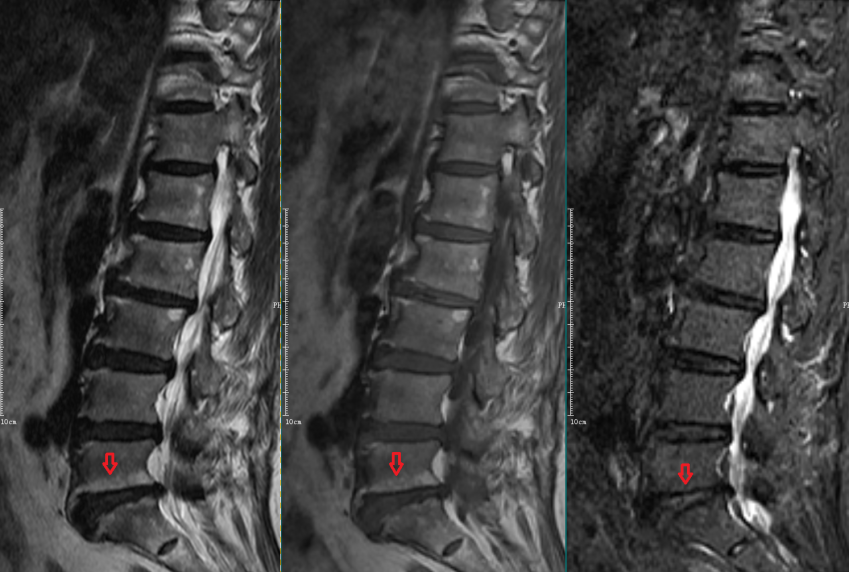

Modic Ⅲ型:

L5-S1椎间盘上下缘见条带状异常信号,T1WI、T2WI及STIR序列均呈低信号。